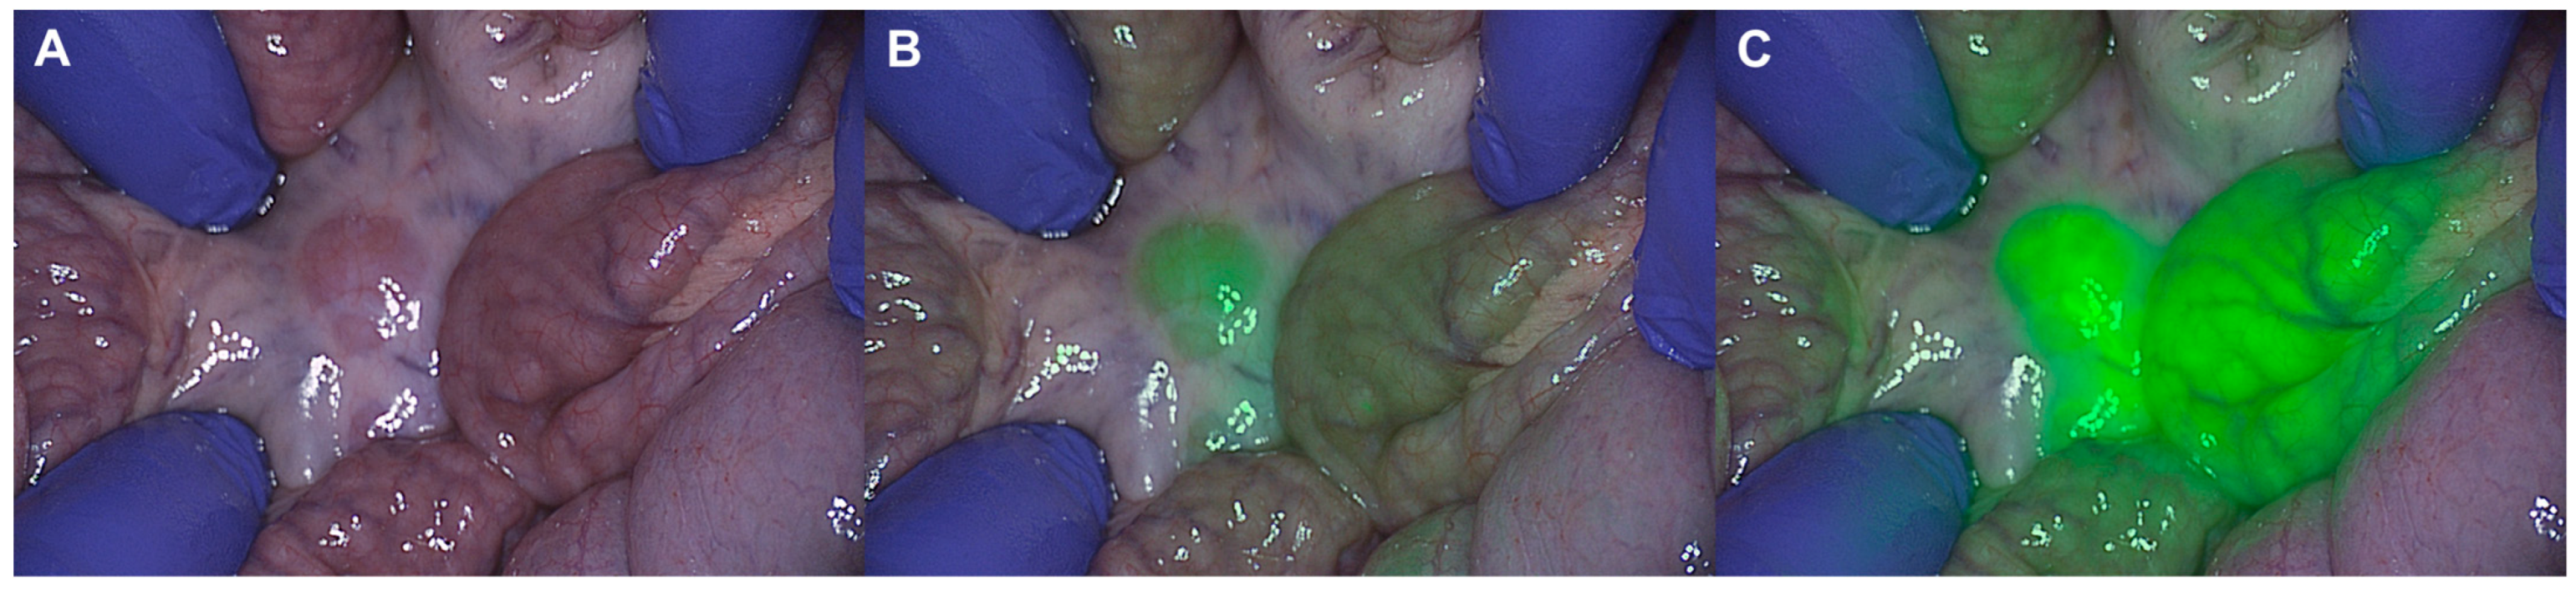

Simultaneous, Multi-Channel, Near-Infrared Fluorescence Visualization of Mesenteric Lymph Nodes Using Indocyanine Green and Methylene Blue: A Demonstration in a Porcine Model

Okamoto, N.; Al-Difaie, Z.; Scheepers, M.H.M.C.; Heuvelings, D.J.I.; Rodríguez-Luna, M.R.; Marescaux, J.; Diana, M.; Stassen, L.P.S.; Bouvy, N.D.; Al-Taher, M. Simultaneous, Multi-Channel, Near-Infrared Fluorescence Visualization of Mesenteric Lymph Nodes Using Indocyanine Green and Methylene Blue: A Demonstration in a Porcine Model. Diagnostics 2023, 13, 1469. https://doi.org/10.3390/diagnostics13081469